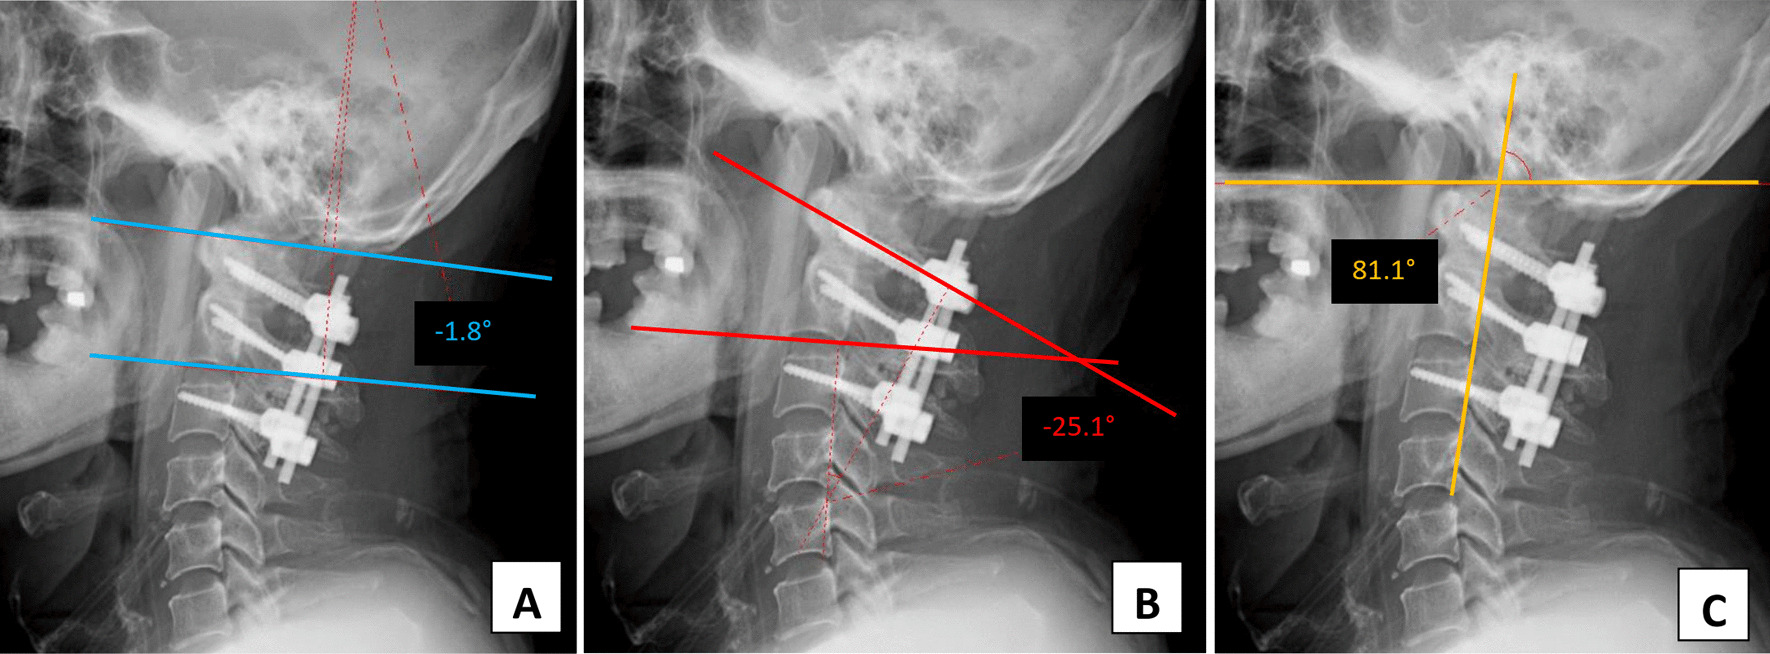

Fig. 5.

Plain radiographs after the second operation show an extended alignment of the upper cervical spine region. The post-correction occiput-C2 angle was − 13.7° (a), the C1–C2 angle was − 32° (b) and the craniovertebral junction angle proposed by Takami was decreased to 76° (c)

Comparison of intraoperative fluoroscopic images before and after adjustment of the implant positions revealed that following the adjustment, the alignment of the C1–C2 level was more extended (Fig. 4). The space of interest behind the mandible associated with the cervical spine and just beneath the occipital bone associated with the screw-rod system was widened. Immediately after the revision surgery, the patient’s trismus and dysphagia symptoms improved drastically. He could swallow 3 and 10 ml of water in a test without coughing or havein g a wet voice. He passed the cup drink test of 30 ml water by straw without choking. As the segment was more lordosis, the occiput-C2 and C1–C2 angles were changed to − 13.7° and − 32°, respectively. At the same time, the craniovertebral angle of Takami was decreased to 76° (Fig. 5).